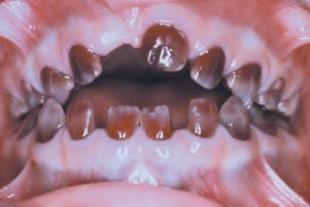

Eruption cyst (EC) | Dentigerous 萌發 | 12a, 12b, 34a, ?6 | 10y ↓ | 藍色或紫棕色 ![]() ![]() |